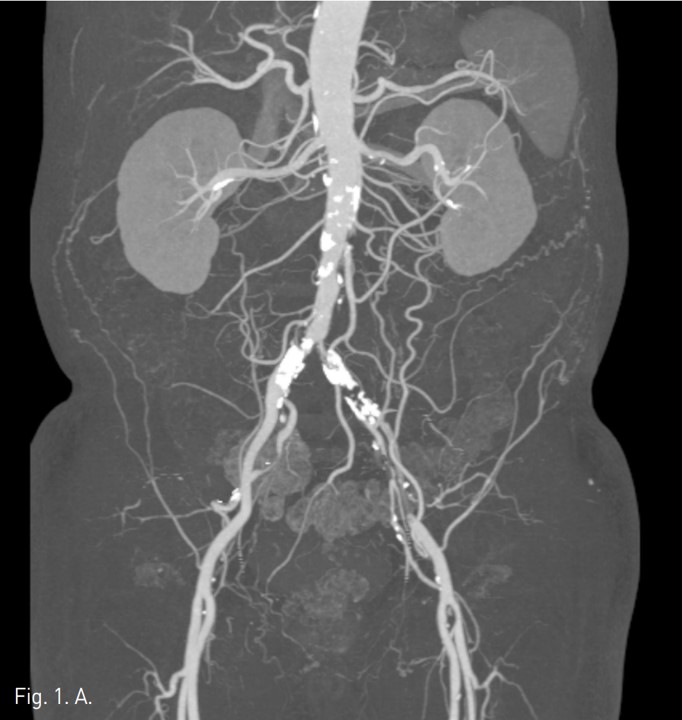

컴퓨터단층촬영 혈관조 영술과 고식적 혈관조영술에서 우측 총장골동맥에 석회화를 동반한 80%정도의 심한 협착이 있고, 좌측 총장골동맥에서 외장골동맥에 석회화를 동반한 완전 폐쇄의 소견이 있다 (Fig. 1A, IB). 우총대퇴동맥의 근위부에 10mm x 29mm Zenesis stent를 설치하였다 (Fig. 2). 0.035 inch guidewire로 좌측 총장골동맥의 기시부 폐쇄부위 통과를 시도하였으나 가성내강에서 진성내강으로 재진입이 되지 않았다 (Fig. 3). 좌측 외장골동맥 진성내강 내에 있는 ‘L-자’ 표시방향의 outback device가 보인다 (Fig. 4A), 좌측 외장골동맥 진성내강 내에 있는 'T-자’ 표시방향의 outback device가 보인다(Fig. 4B). Outback device를 이용하여 동맥내막을 천자후 0.014 inch guidewire를 가성내강 내로 진입시켰지만 좌측 총장골동맥-외장골동맥경 계부위에서 더 이상 진행되지 않았다 (Fig. 4C). 0.014 inch guidewire를 따라서 Davis catheter를 가성내강 내로 진입시키고 (Fig. 5A), 10mm snare를 삽입하여 Simmon catheter내부에 있던 microwire를 전진시켜 snare로 잡아 좌측 sheath로 뽑아내어 (Fig. 5B), 5Fr. Davis catheter를 대동맥 내부로 진입시켰다(Fig. 5C). 양측 총장골동맥 및 좌측 외장골동맥 스텐트 설치후 대동맥장골동맥조영술상에서 양측 장골동맥의 완전한 재개통을 보인다 (Fig. 6).

Fig. 5. A

Fig. 5. A and 5B. Radiograph obtained at the moment of capturing proximal microwire using a snare.

Fig. 5. B

Fig. 5. C

C. Davis catheter was successfully advanced into the aortic true lumen.